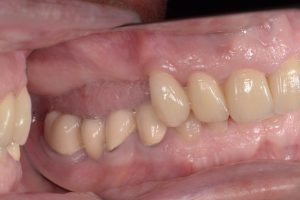

A restauração provisória de longo prazo, uma ponte fresada de cinco unidades feita de resina de alto desempenho com base em PMMA, foi primeiramente verificada quanto ao ajuste e foi fixada aos implantes sem a necessidade de ajustes individuais (Fig. 14). A precisão do fluxo de trabalho digital foi refletida no ajuste exato da restauração provisória.

(Fonte: Dr. Jan Erik Jansohn)

Após um tempo total de tratamento de cerca de 90 minutos, a paciente saiu do consultório sem dor e com os dentes fixos (Fig. 15). Como medida profilática, foram prescritos um analgésico e um antibiótico. Ela também foi aconselhada a favorecer o lado esquerdo da arcada ao mastigar durante o primeiro mês após a cirurgia. No entanto, ela pôde usar a ponte provisória de longo prazo implantossuportada desde o primeiro dia.